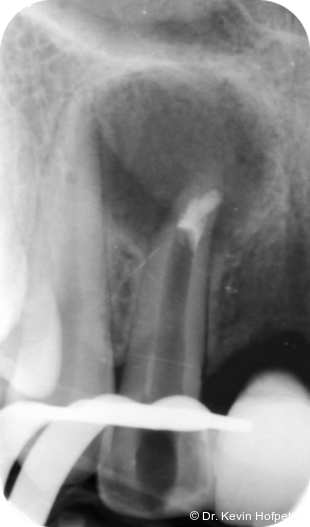

Zwei Monate später konnte die definitive Obturation erfolgen. Da der Kanal nun trocken war, konnte die Dentinbrücke im apikalen Bereich unter Sicht entfernt werden (Abb. 3). Das Mineral Trioxid Aggregat (MTA, Medcem) wurde frisch mit steriler Kochsalzlösung angemischt und mithilfe einer MTA-Gun (MAP-System, Produits Dentaires) sowie individuell angepassten Guttaperchastiften in den gekrümmten Kanalabschnitt eingebracht. Die größte technische Herausforderung bestand im Einbringen eines dichten apikalen MTA-Verschlusses hinter der Kurvatur (Abb. 4). Nachdem dieser Verschluss gesetzt war, wurde der restliche Kanal mit einem Epoxidharz-Sealer (AH Plus, Dentsply Sirona) und erwärmter Guttapercha mittels warm-vertikaler Kompaktion gefüllt und der Zugang adhäsiv verschlossen (Abb. 5).

Kontrollaufnahmen nach drei, sechs, neun, zwölf und 24 Monaten zeigten eine fortschreitende knöcherne Heilung (Abb. 6–10). Die Patientin war beschwerdefrei und zeigte sich mit dem Ergebnis sehr zufrieden. Radiologisch war eine deutliche Rückbildung der Läsion erkennbar, wenngleich eine geringe apikale Aufhellung persistierte. Weitere Verlaufskontrollen wurden empfohlen.